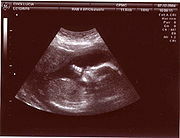

У

льтразвуковое исследование используется для изучения внутренних половых органов женщины, состояния беременной матки, анатомии и мониторинга внутриутробного развития плода.

Плод в утробе матери.

Этот эффект широко применяется в акушерстве, так как звуки, идущие от матки, легко регистрируются. На ранней стадии беременности звук проходит через мочевой пузырь. Когда матка наполняется жидкостью, она сама начинает проводить звук. Положение плаценты определяется по звукам протекающей через нее крови, а через 9 — 10 недель с момента образования плода прослушивается биение его сердца. С помощью ультразвукового исследования можно также определять количество зародышей или констатировать смерть плода.